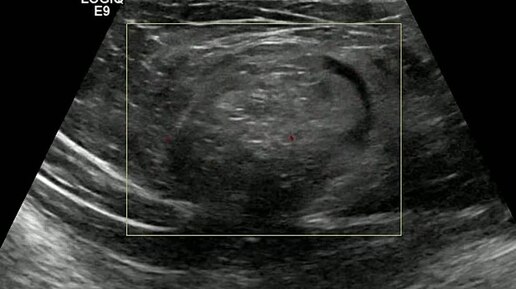

Видео к статье "Ущемленная грыжа белой линии" https://dzen.ru/a/Z4dbuDYQdUQl35Wp

Ультразвуковые находки от врача УЗД Зорина Я.П.